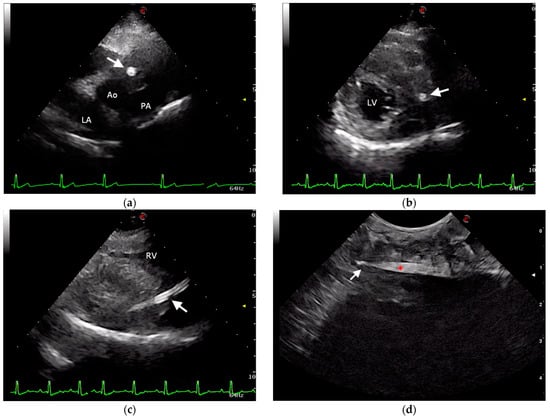

2.1. Case Description and Clinical Investigations

2.2. Surgical Approach and Outcome